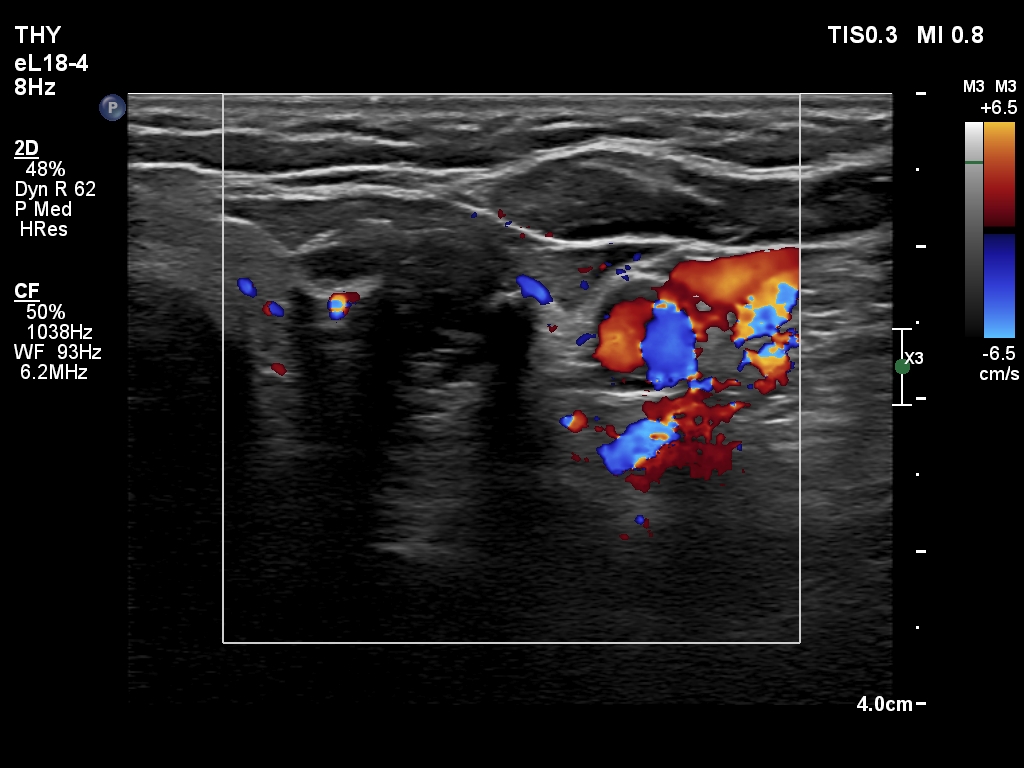

Right lobe, longitudinal scan

Upper-middle part of the left lobe, transverse scan, color Doppler mode. The vascularization is scanty.